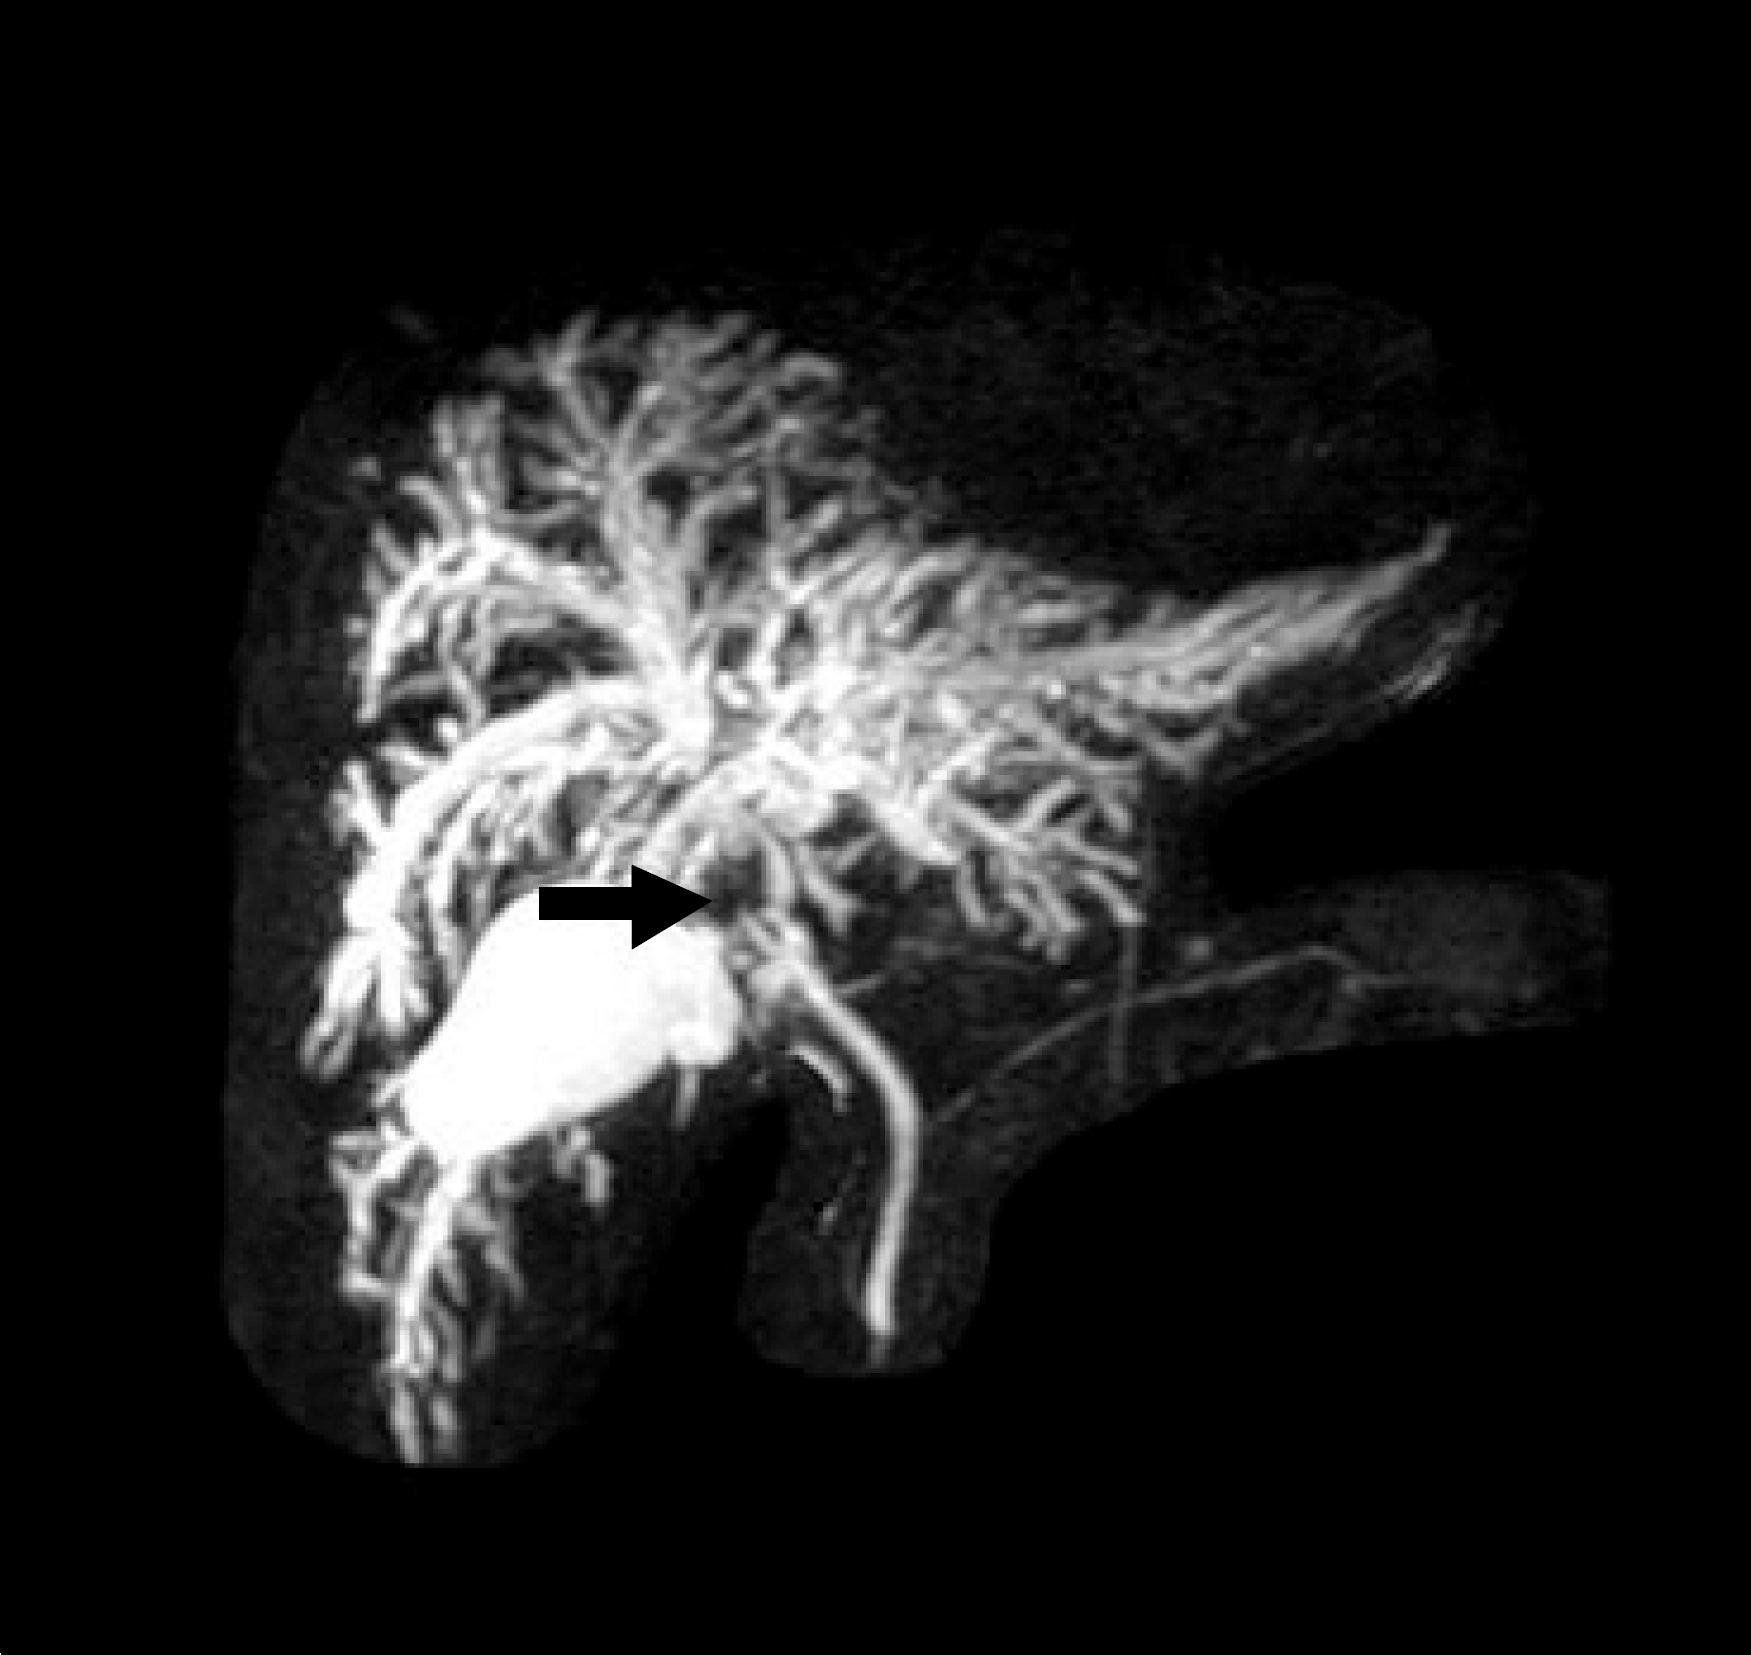

Fig. 2.

Magnetic resonance cholangiopancreatography (MRCP) showed stenosis of the main hepatic duct junction (arrow) with dilatation of intrahepatic bile ducts.